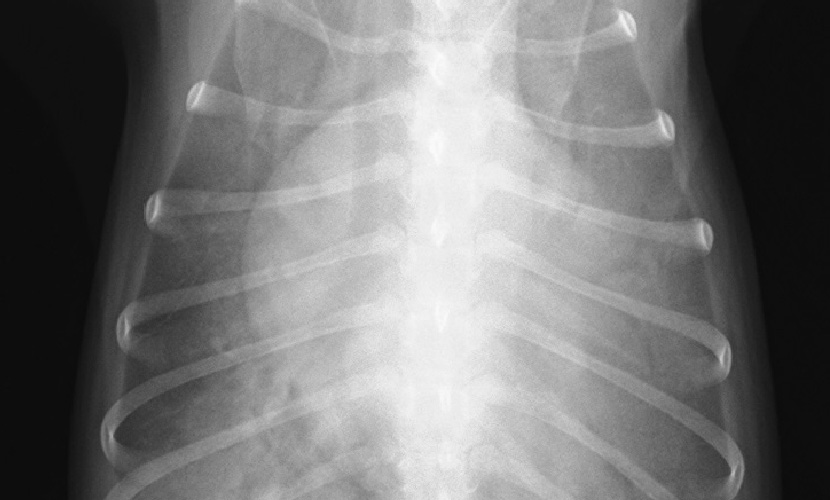

心原性肺水腫(僧帽弁閉鎖不全症)

胸部レントゲン検査

来院と同時に酸素化と利尿剤、鎮静剤投与。Point of care 超音波検査とレントゲン検査にて心原性肺水腫による呼吸不全と診断。一般的な治療への反応に乏しく更に呼吸状態の悪化を認めたため全身麻酔下で人工呼吸管理へ移行。

High PEEP & low tidal volumeでの陽圧呼吸管理にて100%酸素給与下での動脈血酸素分圧(PaO2)197mmHg→595mmHgまで改善し、weaningを経て開始10時間強で人工呼吸管理より離脱。